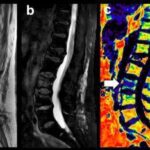

A new tool for the characterization of spine fractures

This simple acquisition, evaluating the amount of fat, is another quick and easy method that helps solve the conundrum of spinal fractures: benign or malignant? Article: Proton density fat fraction (PDFF) MR imaging for differentiation of acute benign and neoplastic...